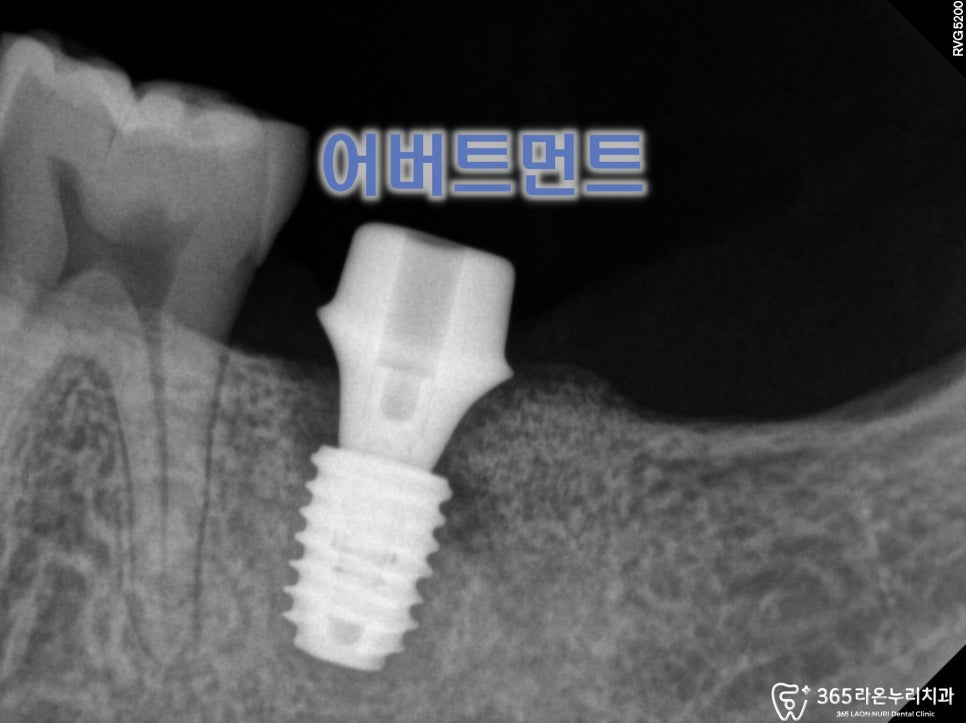

2025.5.18

어버트먼트와 크라운,

최종 보철물 제작이 다 되고 나서

세팅하는 것으로 모든 수술은 끝나게 됩니다.

2025.5.25